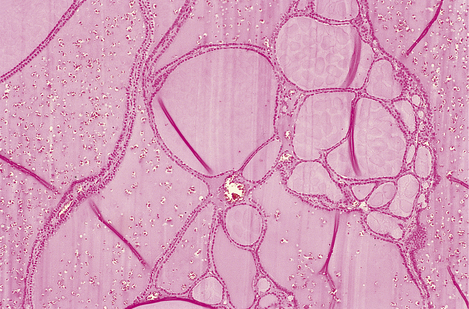

Modern histological classification of the types of hormone-secreting cell is based on immunohistochemistry, a technique in which antibodies raised to a hormone bind to the cells containing that hormone in tissue sections, leading to a coloured stain (Fig. 17.4). This has enabled the true hormone content of the cells to be determined, and has rendered obsolete the traditional classification of the cells into eosinophil, basophil and chromophobe types according to their staining by haematoxylin and eosin (H&E). By electron microscopy, the cells of the adenohypophysis are seen to contain electron-dense granules ranging from 50 to 500 nm in diameter (Fig. 17.5); these contain stored secretory products. The six types of hormone-secreting cell are shown in Table 17.1.

image

Fig. 17.5 Electron micrograph of a secretory cell of the adenohypophysis. The hormonal products are stored as electron-dense membrane-bound cytoplasmic granules (´ 300 000).